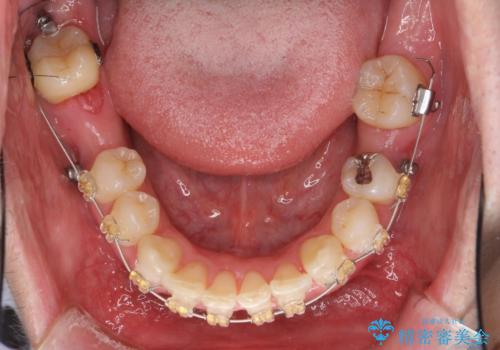

下の歯がないところに、奥歯が倒れこんでいたため、矯正治療で倒れこんだ歯を起こして、インプラントを植立しました。

上顎の小臼歯2本、下顎の親知らずを抜歯しています。

八重歯の移動のため、矯正用ミニスクリューを使用しています。